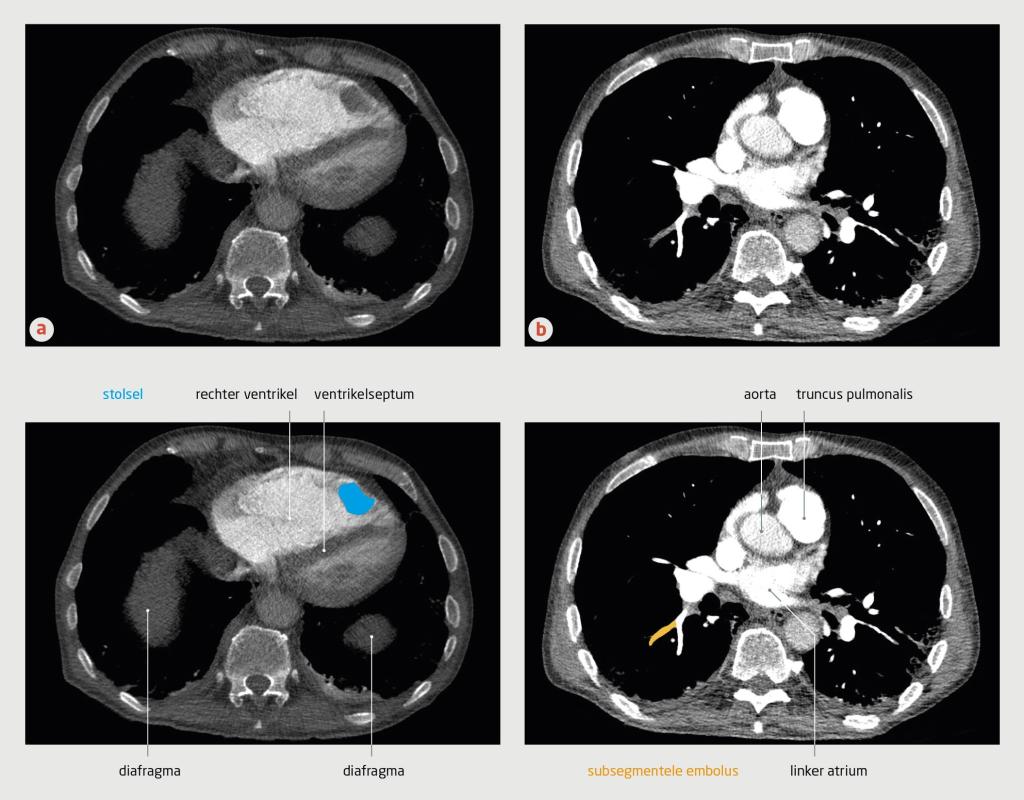

In de verklarende tekening bij figuur 3b van dit artikel zijn enkele structuren onjuist aangegeven. In het onderschrift bij deze figuur staat ten onrechte dat in figuur 3b segmentele embolieën zichtbaar zijn. Hieronder staat de juiste figuur met het correcte onderschrift.

Figuur 3

CT-angiografie van de thorax van patiënt C

CT-angiografie met contrast van patiënt C (transversale coupe). (a) In de rechter ventrikel bevindt zich een stolsel. De rechter ventrikel is vergroot en er is sprake van septumdeviatie, passend bij overbelasting van de rechter ventrikel. (b) Bij deze patiënt was sprake van subsegmentele longembolieën.

Gezien dit klinische beeld, de D-dimeerwaarde van 3,3 mg/l en een sterke verdenking op longembolie werd op grond van het YEARS-algoritme (afkapwaarde voor D-dimeer: 0,5 mg/l) een CT-A verricht. Deze liet multipele segmentele en subsegmentele longembolieën zien, alsmede een stolsel in de apex van de rechterventrikel met een diameter van 3 cm (figuur 3).

Figuur 3 | CT-angiografie van de thorax van patiënt C

CT-angiografie met contrast van patiënt C (transversale coupe). (a) In de rechter ventrikel bevindt zich een stolsel. De rechter ventrikel is vergroot en er is sprake van septumdeviatie, passend bij overbelasting van de rechter ventrikel. (b) Bij deze patiënt was sprake van zowel segmentele als subsegmentele longembolieën.